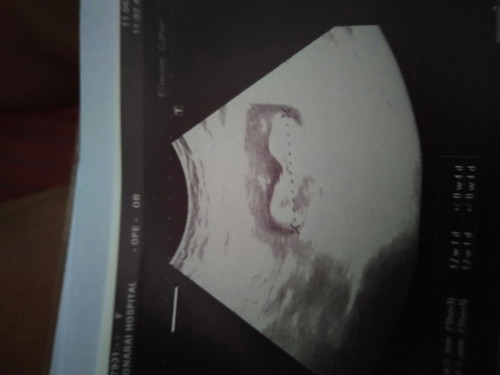

นับตามประจำเดือนได้15w แต่ซาวด์มาได้12+3w เราควรยึดตามอะไรค่ะ

ยึดตามใบซาวด์หมอคะ บ้างทีไข่เราอาจจะตกช้าบ้าง คะ